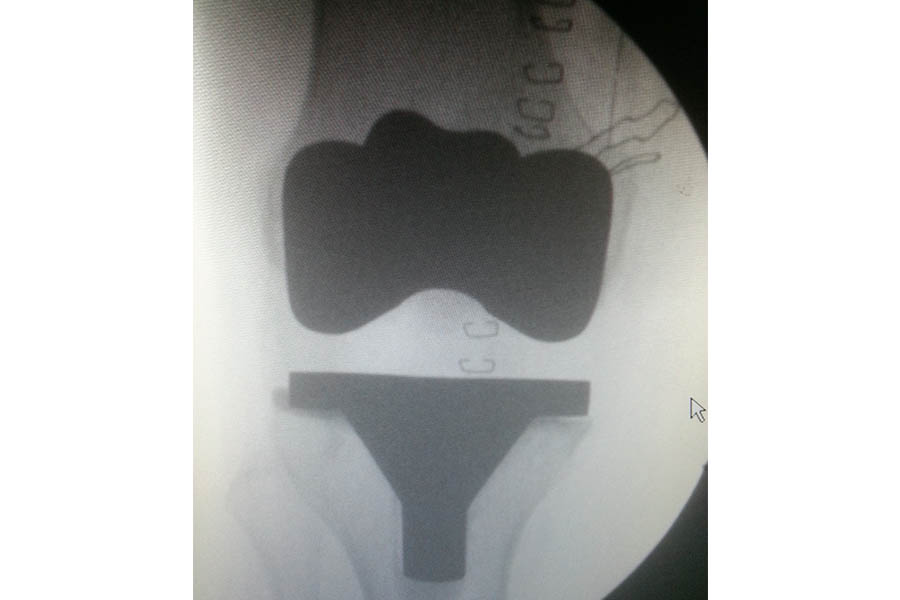

Total Knee Replacement

Case 2